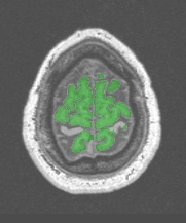

Strange results

the numerous refinements of the simple erosion/dilation procedure allowing robustness to a wide range of images may sometime create strange problems. For instance, with "Robust..." procedures, a piece of white matter may be deleted in corpus callosum and brain stem:

The best solution is the use of the simplest variants:

"Fast (2mm erosion)"

"Fast (2.5mm erosion)"

"Fast (3mm erosion)"